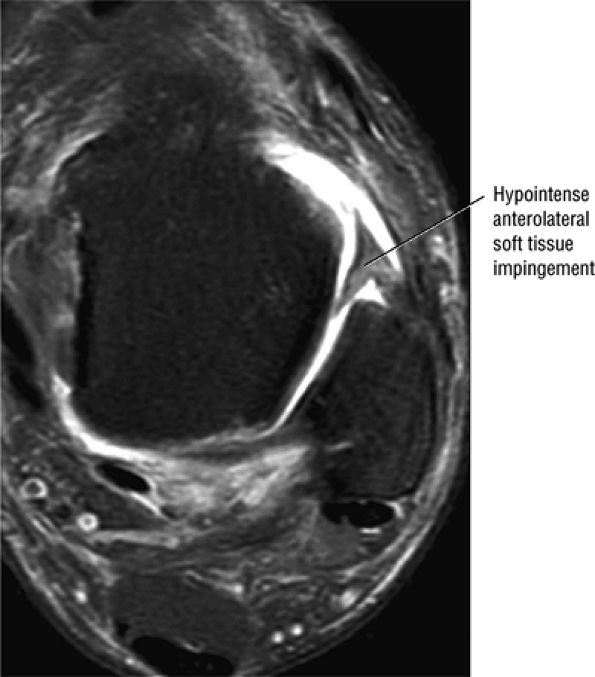

FIGURE 5.29 Impingement.